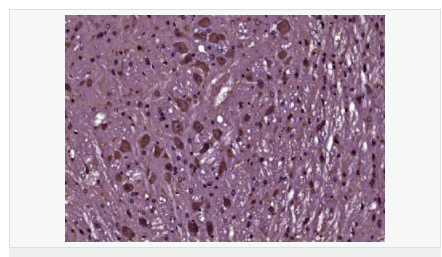

產(chǎn)品介紹BCL2 is an integral outer mitochondrial membrane protein that blocks the apoptotic death of some cells such as lymphocytes. Constitutive expression of BCL2, such as in the case of translocation of BCL2 to Ig heavy chain locus, is thought to be the cause of follicular lymphoma. Two transcript variants (alpha and beta) produced by alternate splicing, differ in their C-terminal ends. BCL2 suppresses apoptosis in a variety of cell systems including factor-dependent lymphohematopoietic and neural cells. It regulates cell death by controlling the mitochondrial membrane permeability. It appears to function in a feedback loop system with caspases. BCL2 inhibits caspase activity either by preventing the release of cytochrome c from the mitochondria and/or by binding to the apoptosis-activating factor (APAF1). It can form homodimers, and heterodimers with BAX, BAD, BAK and BclX(L). Heterodimerization with BAX requires intact BH1 and BH2 domains, and is necessary for anti-apoptotic activity.